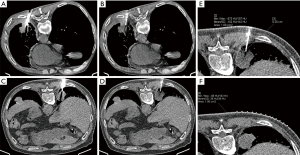

Depending on the location of the lesions, the patient was placed in the supine, prone, or lateral decubitus position. Needle pathways were selected based on a pre-procedural CT scan to avoid any necrotic regions. The scan area was limited to the lesion area, and the free-breathing mode was employed to decrease the psychological burden on patients. After each needle adjustment step, the needle position was determined by scanning the lesion area using the pre-set CT scan protocols (Figure 2). Once the tip of the needle entered the lesion, samples were obtained. To assess post-procedural complications, after the removal of the needle, one final post-biopsy scan of the whole lung was obtained from each patient using routine-dose parameters. The sample was then sent to the pathology department immediately.

Objective image quality evaluation

All values were measured on the soft-tissue convolution kernel (Br40) image. CT values (HU) and image noise [standard deviation (SD) of measured HU values] were determined on the reconstructed 1.5-mm axial CT images using similar (1.0 cm2) ROIs within the thoracic aorta and the air space outside the anterior chest wall for all patients (Figure 2E). Each ROI was placed in an identical or almost identical segment by two operators (with 5 and 3 years of experience in CT imaging, respectively). Contrast in chest CT mainly exists due to the difference in attenuation between the pulmonary vasculature, the surrounding parenchyma, and air. As lung tissue could not be obtained from the same area in different patients due to the limitation of scanning range and individual heterogeneity, image noise was considered as the SD of CT attenuation and was measured within the air space outside the anterior chest wall. Finally, the contrast-to-noise ratio (CNR) and figure-of-merit (FOM) were calculated for each image dataset using the equations below. The FOM is a metric used to compare the dose efficiency of two scanning protocols.

Metal artefact evaluation

Metal artefacts were quantified using CT number reduction (CTNR) and metal diameter blurring (MDB) at the soft tissue window. The mean CT number of lesions was obtained using a 10-mm-diameter ROI at the lesions with the most obvious streak artefacts. The mean CT number over the ROI was measured using the pre-procedural CT scan (no metal) and a second scan that included metal (Figure 3E,3F). The CTNR was then calculated for each metal scan using the following equation: CTNR = HU (metal-image) – HU (baseline image). The outer needle was evaluated. The metal diameter accuracy was calculated from the image data by measuring the width of the needle profile at the cross-sections (Figure 3E) and comparing it to the true outer diameter of the actual needle (16,17) using the following equation: MDB = (Width (image)−Width (true)/Width (true)). Lower values for CTNR and MDB indicate fewer artefacts and higher image quality.

The scores for images with iMAR were higher than those without iMAR (group A vs. group B, or group C vs. group D, adjusted P<0.01), which suggested that the qualitative image quality of CT with iMAR was superior to that without iMAR (Figures 2,3).